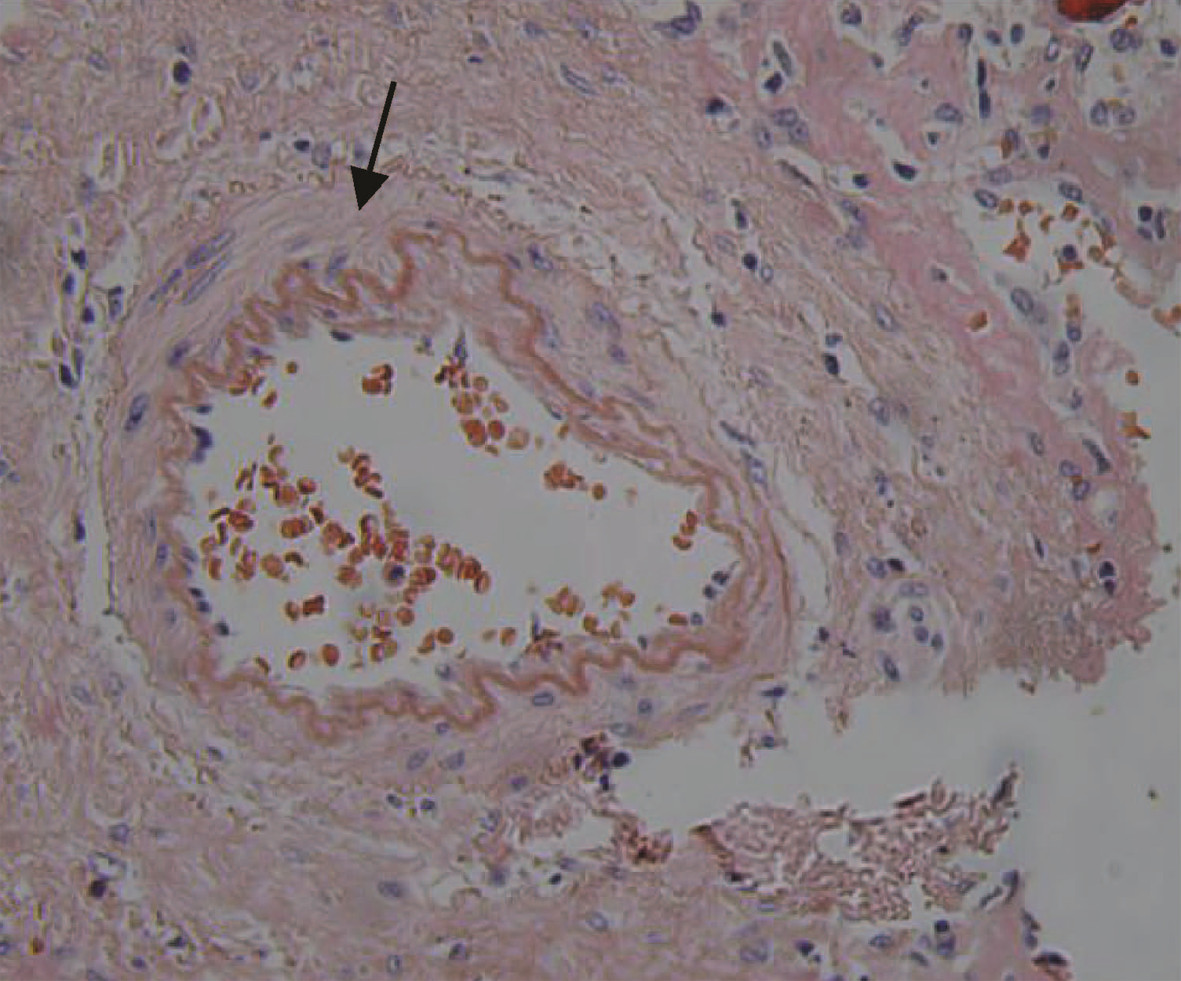

Hepatocellular carcinoma with bile duct tumor thrombus: A case report

Renjie LU, Fangfang SUN, Jie DU, Lirong ZHAO

2022, 38(8): 1872-1874. DOI: 10.3969/j.issn.1001-5256.2022.08.028

Abstract(831) HTML (461) PDF (3665KB)(88)